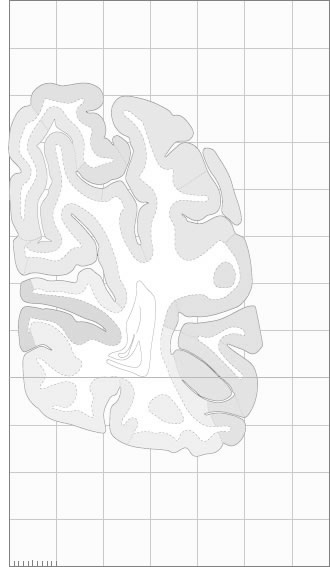

Hi-Resolution Sections · Cells (Nissl Staining) · Virtual Microscopy

Frontal sections (Nissl) from the Atlas Brain:

Macroscopy

Schematic

Slice ID:

r5-0250

Plate NR:

65-66

Position:

83,8 mm